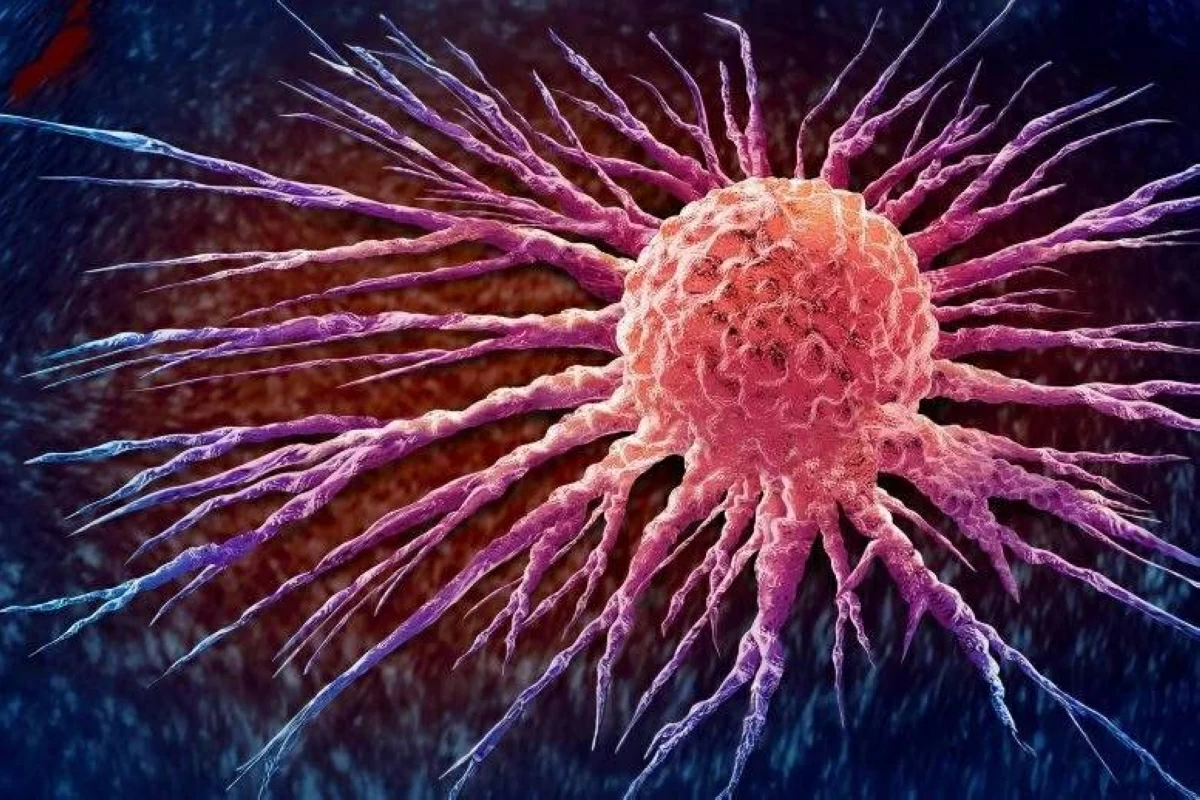

بنوم بنه - أ ف ب أعلن ملك كمبوديا نورودوم سيهاموني، الجمعة، إصابته بسرطان البروستاتا، مشيراً إلى أنه سيبقى في الصين لفترة علاج مطوّلة. وقال الملك البالغ 72 عاماً في بيان موجّه إلى شعبه، إن أطباء في بكين «أكدوا أنني مصاب حالياً بسرطان البروستاتا»، مضيفاً أنهم أوصوا بدخوله...